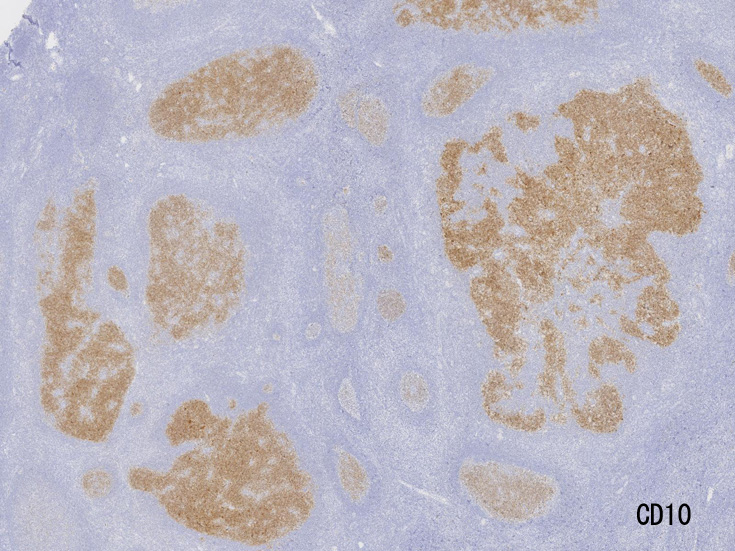

不整形の胚中心(CD20+, CD10+, BCL2-)のまわりにはCD5陽性リンパ球が多く存在してマントル層を形成している. (IgD染色でもマントル層はよく認識できる). 胚中心内のCD5+ cellはfollicular helper T-cellのようです.

大きな胚中心を持つ多数のリンパ濾胞が見られる。胚中心の辺縁は不明瞭でマントル層も薄くなっている。1カ所マントル層リンパ球の侵入によりバラバラになった巨大な胚中心が認められ, macrofollicular patternと記載されるPTGCです。

鑑別にあがるfollicular lymphoma floral variantは全ての濾胞が腫瘍性であり, 本症例では除外可能と考える。

Diagnosis: Reactive lymphadenitis with PTGC